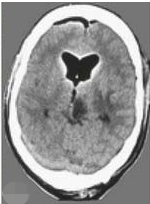

手術(shù)后的計算機斷層掃描證實了病變的完全切除(圖:5)。組織學檢查證實了間變性膠質(zhì)瘤的存在,除了手術(shù),患者還接受了隨后的放化療。

圖5:術(shù)后CT